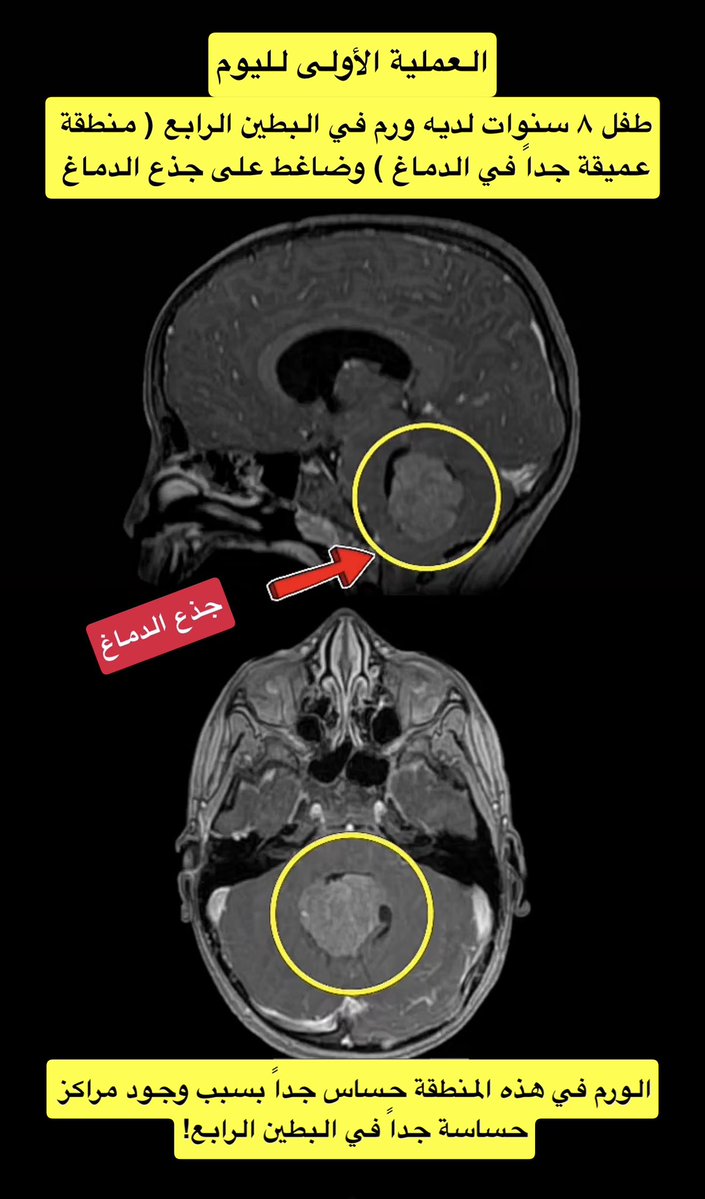

الدكتور #هاني_الجهني استشاري المخ و الاعصاب بغرفة العمليات يجري عملية ازالة ورم من قاع الدماغ لطفل عمره ٨ سنوات . اجريت العملية

بوضع الجلوس للمريض و الجراح

يقف على ركبتيه ..